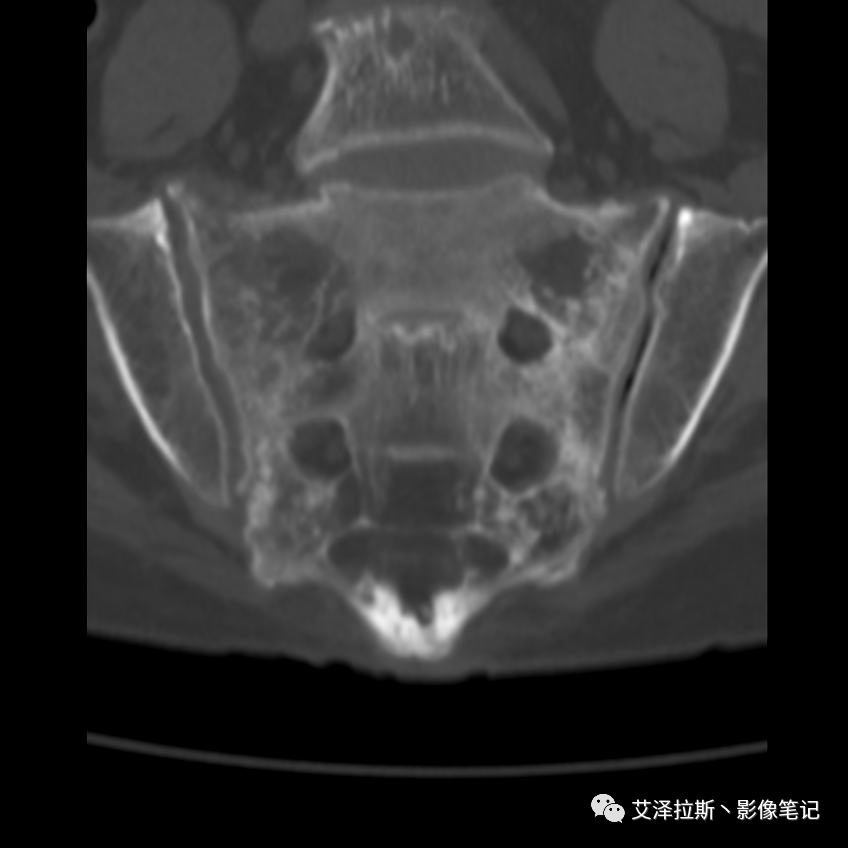

病例2:患者,女性,69岁,老年性骨质疏松症。

病例2

CT平扫:

影像所见

X线、CT:骶骨重度骨质疏松,双侧骶骨翼皮质断裂,分别见迂曲走行的纵行透亮线位于骶孔外侧,大致与骶髂关节间隙平行,骨折端局部可见骨痂、骨质硬化。

诊断意见

骶骨功能不全骨折

②骨折线位于骶孔外侧(如下图,主要发生于1区),通常可能会伴随耻骨的功能不全骨折(如:病例2 右侧耻骨上支骨折,L5双侧横突骨折);